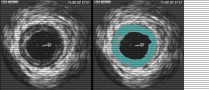

Intravascular Ultrasound (IVUS) and Optical Coherence Tomography (OCT) Core Laboratories

We offer the following IVUS and OCT core laboratory services:

- Assessment of plaque volume

- Assessment of stent underexpansion